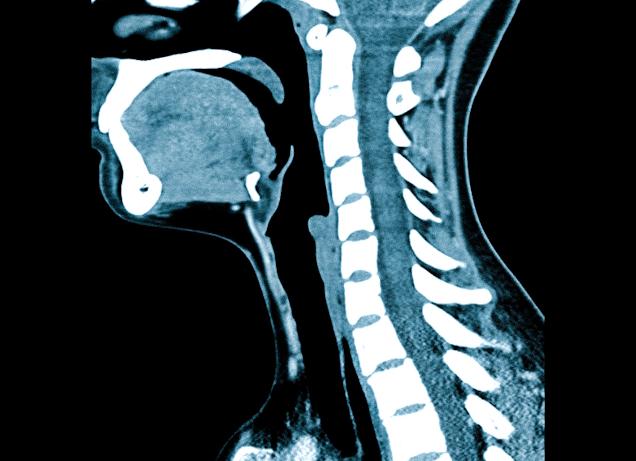

Что выбрать: МРТ или рентген шейного отдела? Отвечая на этот вопрос, многие специалисты сходятся во мнении — каждая из процедур имеет ключевые особенности в сфере диагностики. Так МР-сканирование показало свою эффективность при выявлении патологий мягких тканей позвоночного столба, а рентгенодиагностика информативнее при травмировании, кровотечениях.

Когда необходимы МРТ или рентген шейного отдела, нужно понимать, в чем основные преимущества и недостатки обеих методик. Магнитно-резонансная томография использует мощное магнитное поле, которое особым образом влияет на атомы водорода, содержащиеся в тканях организма. Во время сканирования томограф посылает серию радиочастотных импульсов, что приводит к возникновению ядерного магнитного резонанса и изменению электромагнитного отклика атомных ядер. Измененные параметры фиксируются компьютерным оборудованием, проходят сложную обработку и преобразовываются в трехмерное изображение зоны интереса.

Рентген шейного отдела содержит в основе иной принцип. Конечные снимки получают в результате ослабления рентгеновских волн при прохождении в средах с разной плотностью. На рентгенограмме кости изображены в виде участков белого цвета, воздушные полости — черного, а мягкотканные структуры приобретают различные оттенки серого.

Шейный отдел позвоночника состоит из семи позвонков и считается наиболее подвижным. Через него проходят кровеносные сосуды, участвующие в кровоснабжения мозга, поэтому своевременная диагностика любых патологических процессов в этом участке тела крайне важна. Выбирая между МРТ или рентгеном шейного отдела, врач собирает анамнез, оценивает симптоматику и выявляет возможные противопоказания.